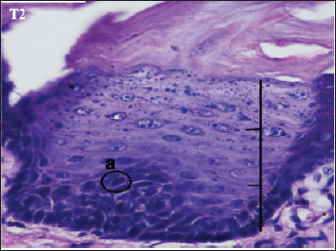

Fig. 4. Histopathological description of the rat tongue epithelium in the T2 group, microscope at ×400. (a) Variations in cell shape with hyperchromatic nuclei.

The histopathological appearance of the rat tongue epithelium in the T2 group showed irregular stratified cells. In the basal and parabasal layers, upwards to one-third of the thickness of the epithelium reveals differences in the form and size of cells and nuclei. Hyperchromatic nuclei were found in the epithelium’s basal and parabasal layers, which do not extend beyond the lowest one-third. The layers of spinosum and granulosum had no dysplastic cells (Fig. 4).